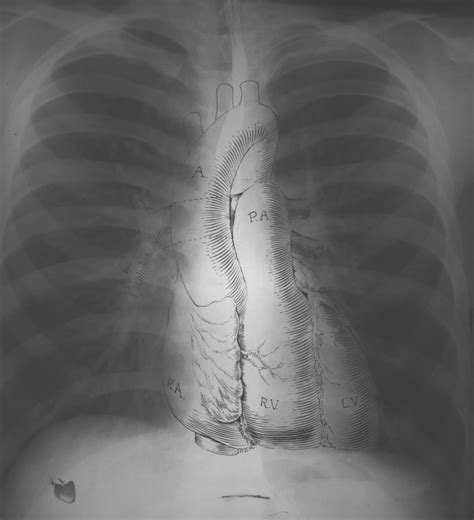

What Does a Normal Chest X-Ray Look Like?

Okay, so what exactly are doctors looking for when they say an X-ray is “normal”? Basically, a normal chest X-ray shows clear lungs, a heart of normal size and shape, and healthy-looking blood vessels. The bones, like your ribs and spine, should also appear intact and without any signs of fractures or abnormalities. Think of it like a well-organized room – everything is in its place, and there’s nothing out of the ordinary catching your eye.

The Heart

The heart should appear in the center of the chest, slightly to the left. Its size and shape should be within normal limits. An enlarged heart, or cardiomegaly, can be a sign of heart failure or other cardiovascular problems. The heart’s borders should be well-defined, and there should be no unusual bulges or indentations. Doctors also assess the position and size of the great vessels , such as the aorta and pulmonary artery. Any abnormalities in these structures could indicate congenital heart defects or other vascular conditions. In addition to the heart itself, doctors also look at the surrounding structures, such as the pericardium (the sac that surrounds the heart). Inflammation of the pericardium, known as pericarditis, can cause fluid to accumulate around the heart, which may be visible on a chest X-ray. By carefully examining the heart and its surrounding structures, doctors can gain valuable insights into the patient’s cardiovascular health.